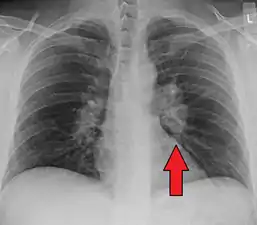

Chest X-ray showing the typical nodularity of sarcoidosis, predominantly in the hila of the lungs.

Chest radiograph changes are divided into four stages:[105]

1. bihilar lymphadenopathy

2. bihilar lymphadenopathy and reticulonodular infiltrates

3. bilateral pulmonary infiltrates

4. fibrocystic sarcoidosis typically with upward hilar retraction, cystic and bullous changes

Although people with stage 1 radiographs tend to have the acute or subacute, reversible form of the disease, those with stages 2 and 3 often have the chronic, progressive disease; these patterns do not represent consecutive "stages" of sarcoidosis. Thus, except for epidemiologic purposes, this categorization is mostly of historic interest.[28]